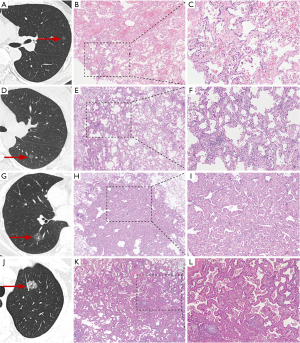

CT radiological features

Figure 2 displays the pathological results corresponding to different SPN lesions, and Figure 3 provides examples of qualitative features in CT images. Inter- and intrareader agreement analyses for all CT imaging features demonstrated excellent consistency (all Cohen’s κ and ICC >0.8). As shown in Table 2, statistically significant differences (P<0.01) were observed between Group A and Group B in the training and testing datasets for pulmonary nodule imaging characteristics, including maximum diameter, density type, shape, spiculation, pleural retraction, lobulation, and air bronchogram, while there were no significant differences in other features. Except for density type, no statistically significant differences (P>0.05) were found in imaging characteristics between the training cohort and external testing cohort.